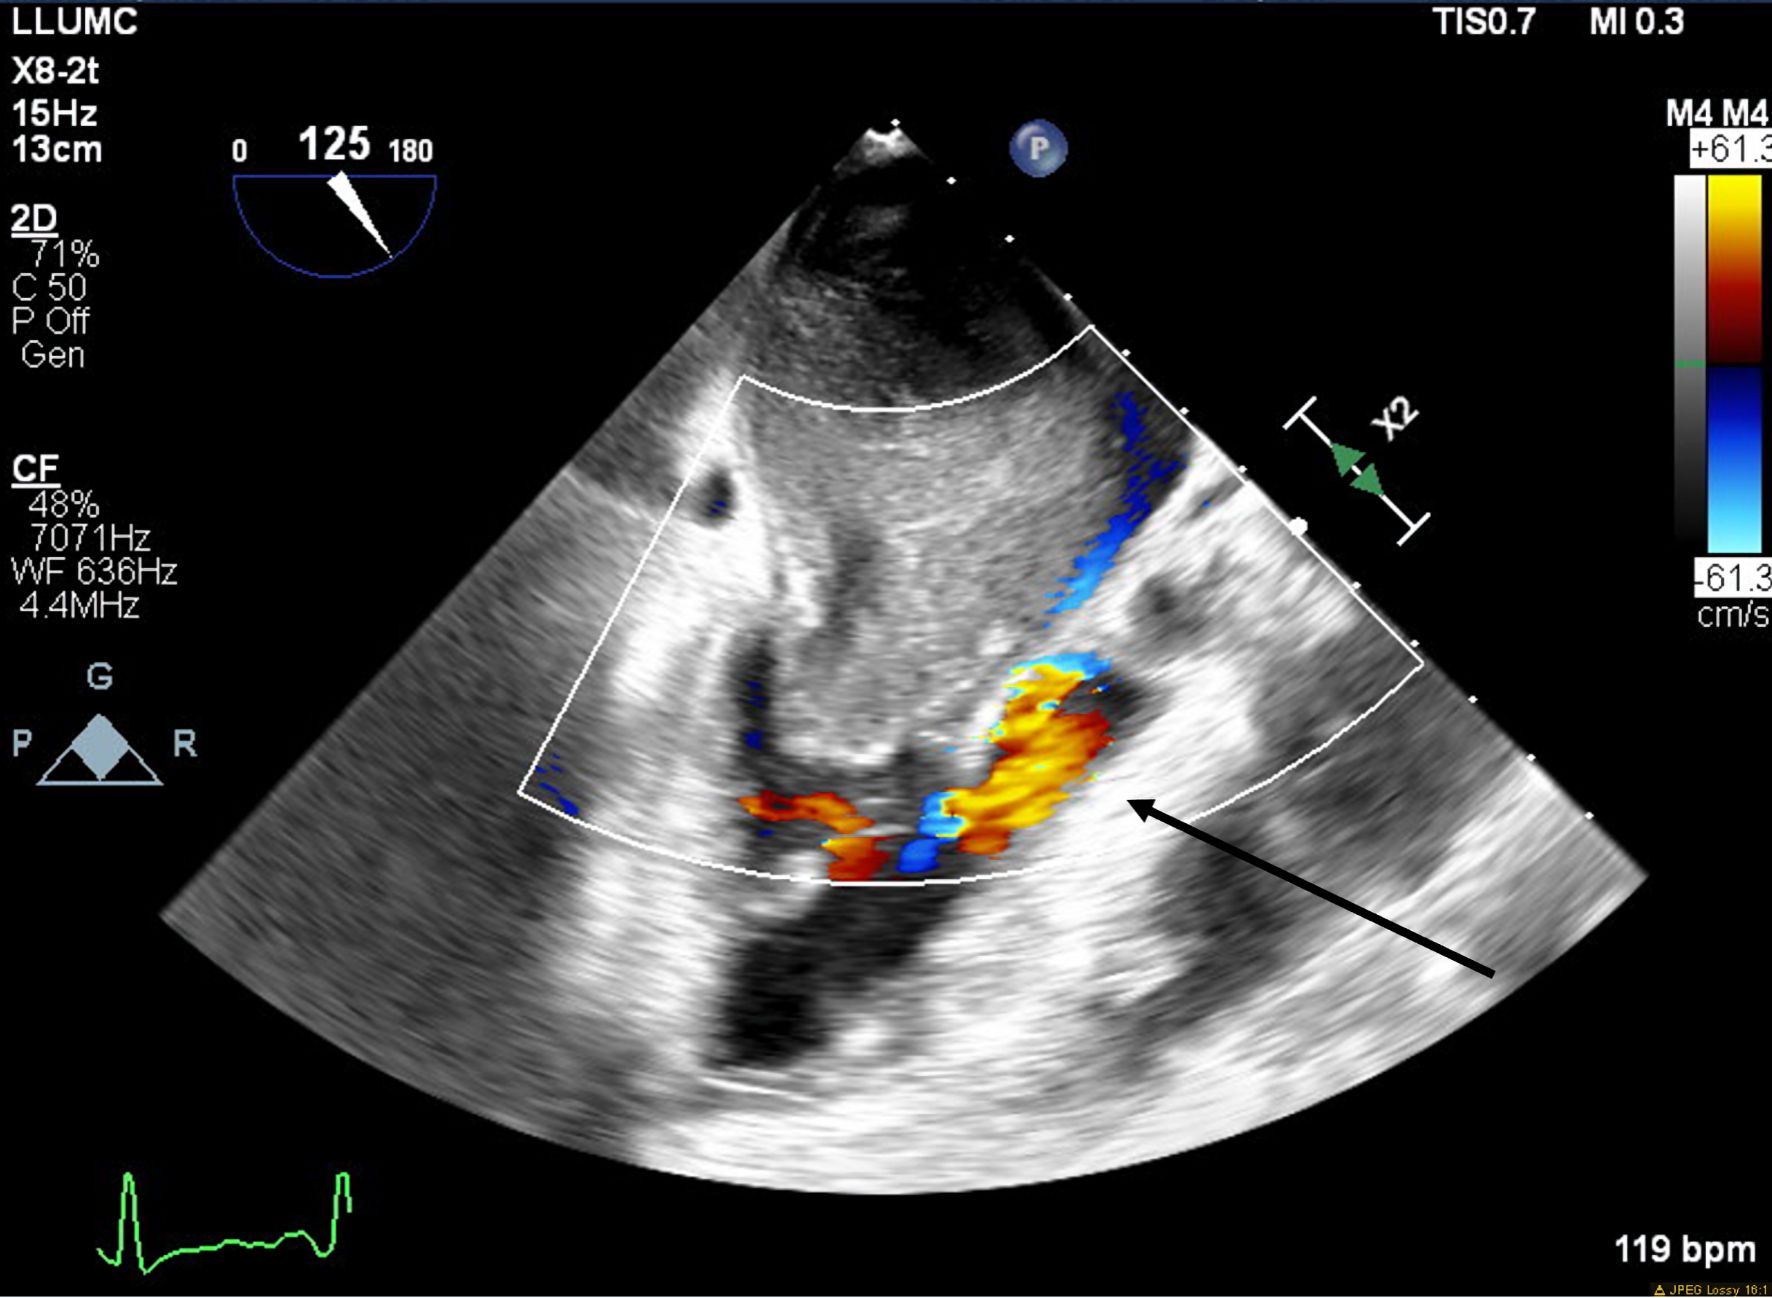

A 66-year-old obese woman presented to the emergency department (ED) with a 2-month history of progressive fatigue, 20-lb weight loss, orthopnea, wheezing, chest pressure, lower extremity edema, dyspnea on exertion, and paroxysmal nocturnal dyspnea. On examination, she had a systolic murmur. Transthoracic echocardiography (TTE) revealed a 5-cm mass occupying her left atrium. Right and left heart catheterization showed no flow-limiting coronary artery disease. Right heart pressures were as follows: right atrium 3 mm Hg, right ventricle 66/4 mm Hg, pulmonary artery 67/25 mm Hg, pulmonary capillary wedge pressure 25 mm Hg, and left ventricle 103/9 mm Hg. With plan for further workup, she was discharged and scheduled for elective resection. She returned to the ED 5 days later with severe acute hypoxic respiratory failure. On admission, vitals were as follows: heart rate (HR) 129, respiratory rate (RR) 44, SpO2 92%, and blood pressure (BP) 110/70. Her hypoxemia was managed with high-flow nasal cannula, and she was scheduled for urgent resection of her left atrial mass. In the operating room, she was severely orthopneic when the head of her bed was lowered below 90°. A radial arterial and internal jugular central venous catheter were placed while she was in a seated position on high-flow nasal cannula (fraction of inspired oxygen (FiO2) 100%, 35 liters per minute (LPM)). Femoral central venous and arterial cannulas were also placed prior to induction of anesthesia to enable emergent transition cardiopulmonary bypass (CPB). A dexmedetomidine infusion was used to facilitate vascular cannulation, surgical preparation, and draping. Vasopressin, epinephrine, and norepinephrine infusions were started preemptively, and she received a 250-mL albumin bolus. Her airway was secured with video laryngoscopy after induction with etomidate and rocuronium. After induction, she became profoundly hypotensive and hypoxemic, with mean arterial pressure (MAP) dropping by 30 mm Hg and oxygen saturation dropping to 70%. This brief episode resolved with administration of crystalloid, vasopressin boluses, and Trendelenburg positioning. Despite a transient period of hypotension and hypoxia, emergency CPB was not required. A median sternotomy was performed, and she was transitioned to CPB by aorto-bicaval cannulation. Intraoperative transesophageal echocardiography (TEE, X8-2t, EPIQ CVx; Philips Ultrasound, Bothell, WA) redemonstrated a large pedunculated mass traversing the interatrial septum and occupying the right and left atria. Mid-esophageal views were used to image the large heterogeneous mass (Figs. 1, 2). She was found to have a 7 × 4.5 cm left atrial mass arising from the lateral wall of the atrium near the left inferior pulmonary vein. Pulmonary venous return was obstructed, likely contributing to her pulmonary hypertension, pulmonary edema, and hypoxemia. During atrial systole, the mass traversed the mitral valve orifice and obstructed mitral inflow and the left ventricular outflow tract (LVOT). LVOT obstruction persisted during early ventricular systole, and flow acceleration was observed with color flow doppler (Figs. 3-5).

Figure 3. Mid-esophageal aortic long-axis view showing a mass obstructing the left ventricular outflow tract (LVOT) during early systole. The arrow indicates LVOT obstruction.

Figure 4. Mid-esophageal two-chamber view with color flow Doppler demonstrating turbulent flow around the mass through the mitral valve during diastole. The arrow indicates turbulent flow through the mitral valve.